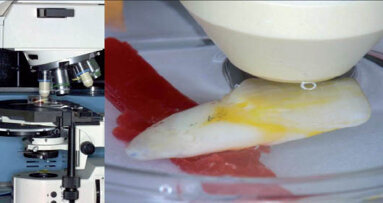

Konstrukce lešení vhodného pro speciální účely. Buňky jsou rozprostřeny na povrchu trámce scaffoldu. Reakce buněk je pozitivní.

Mezi trámci scaffoldu se vytváří buněčné můstky. Pokud je lešení degradovatelné, buňky vytváří náhradní tkáň.

Rozemletá tvrdá zubní tkáň ve zkouškách in vitro s buňkami MG63. Je vidět afinita buněk k některým zrnům tvrdé zubní tkáně.

Afinita k zrnům tvrdé zubní tkáně je vidět na zrnu, které je obaleno buňkami. Předpokládáme, že toto zrno je dentin. Velké zrno v pravé části obrazu je bez buněčného obalu. Předpokládáme, že jde o sklovinu.

Mezi zrny tvrdé zubní tkáně se poměrně rychle (cca do 24 hodin) vytváří ucelený buněčný můstek, což může znamenat rychlou tkáňovou reakci

Stomatologické výzkumné centrum pod vedením prof. Jiřího Vaňka udělalo pro takové dynamické metody potřebný základ. Bylo ověřeno mnoho základních materiálů pro dentální implantologii a ve spolupráci s výrobními organizacemi a akademickou sférou přispělo k tvorbě zcela nové slitiny pro implantáty. Mnoho otázek však zůstalo otevřeno. Jednou z nich je otázka charakteru povrchu, popřípadě interakce buněk na rozhraní dvou tkání. Přináší to další výzkumné otázky, kladené zejména akademické sféře optických dovedností, to je záznam přímého snímkování chování buněk na neprůhledných površích za současného zviditelnění průsvitných buněčných těl.

Vedle materiálů umělých, obvykle slitin kovů, popřípadě upravených plastických hmot, je však i zcela reálná cesta k využití buněk či orgánů tělu vlastních. To platí nejenom pro aplikace implantologické, ale i pro celou oblast reparace ať již tkáňové nebo buněčné. Jednou z nich je metoda využití dentinu pro augmentaci kostní tkáně, která je už v současnosti využívána ve stomatologii. Její princip je v rozemletí očištěného zubu na úlomky velikosti přibližně 300 μm a jejich aplikaci do zubní jamky, kde tento materiál prostor vyplní a umožní po krátké době další operační zásahy. Jde tedy o skutečný biomateriál s okamžitou aplikací, popřípadě o jeho uchování k aplikacím pozdějším.

Otázkám přijatelnosti rozemleté zubní tkáně byla věnována pozornost i na vývojovém pracovišti stomatologické kliniky LF MU v Brně a v Laboratoři tkáňových kultur Jihočeské univerzity v Nových Hradech. V podmínkách in vitro byla potvrzena hypotéza o přijatelnosti pomleté tvrdé zubní tkáně kostními buňkami, pochopitelně v modelových pokusech. Bylo nastoleno mnoho dalších výzkumných otázek, které jsou postupně řešeny nejenom na úrovni laboratorní, ale i klinické.